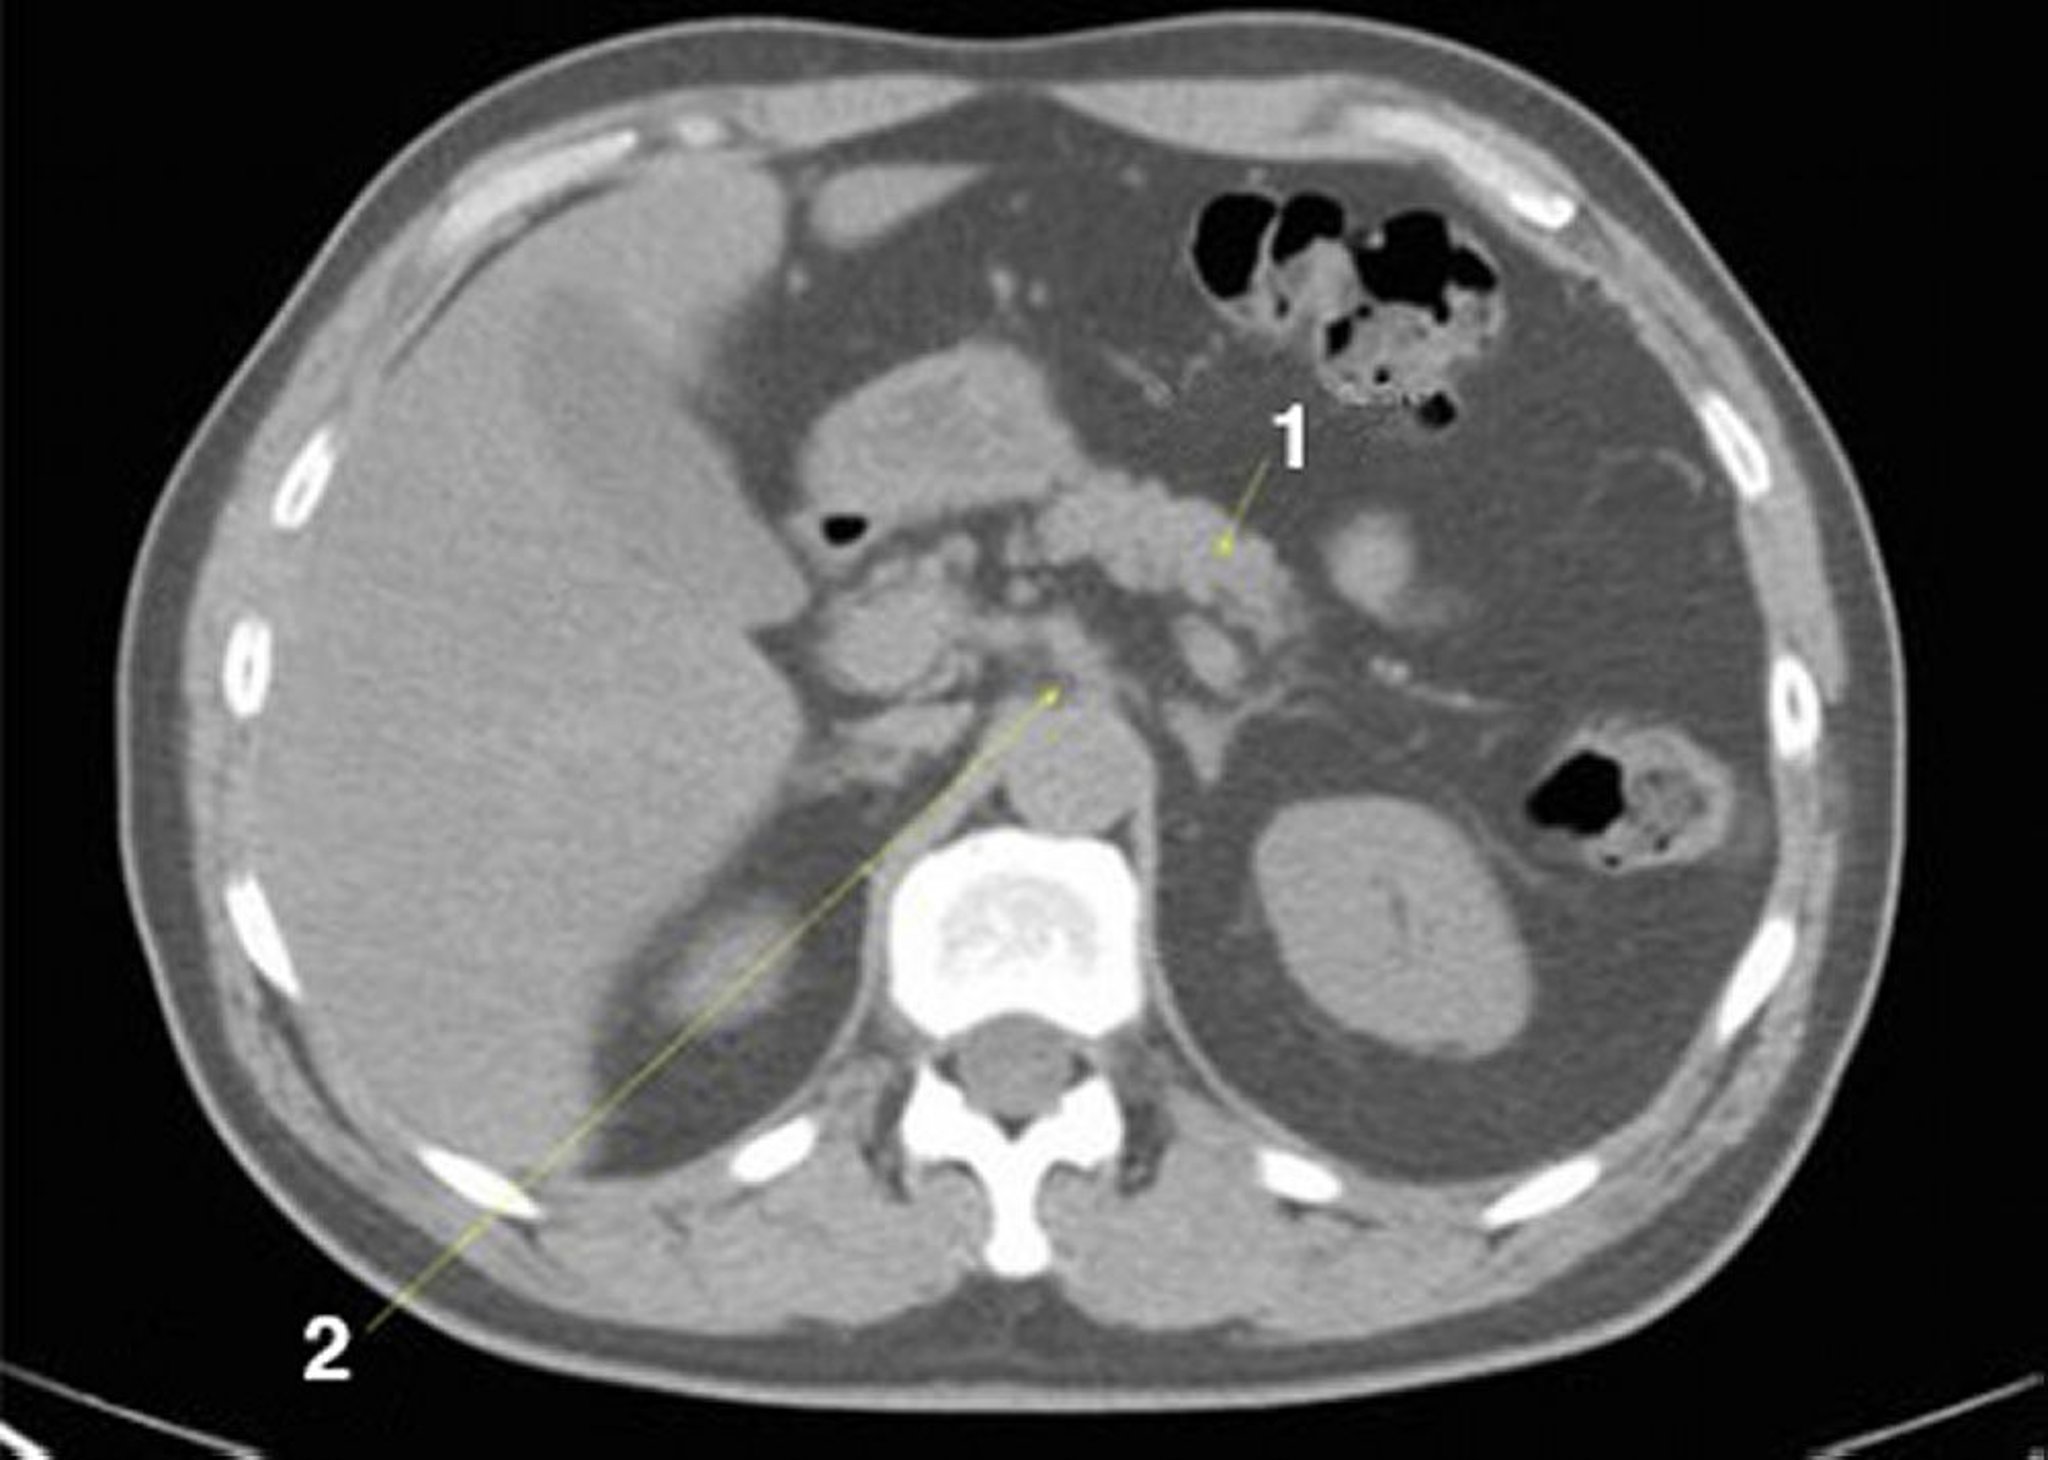

TC sem contraste do abdome e da pelve mostrando anatomia normal (lâmina 9)

1 = pâncreas; 2 = eixo celíaco.